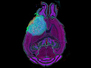

Crossing the Node

Nerve axons – slender projections, the route of signals from neurons to other cells – are insulated with a sheath called myelin to ensure signals stay on track, however, there are specialised gaps in the wrapping at Nodes of Ranvier which aid signal conduction. This study, using time-lapse microscopy in live mice, investigates how these nodes impact the essential transport of neurons' contents such as mitochondria (highlighted here in cyan) and endosomes (in magenta) along the axons, providing insight into nerve function in health, injury and disease